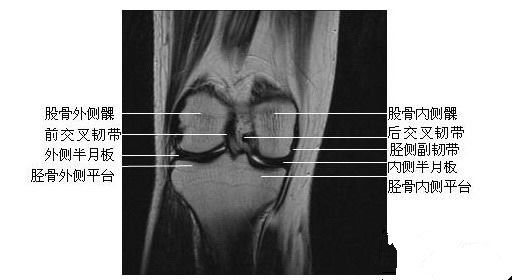

膝关节冠状面(三)

膝关节冠状面(四)